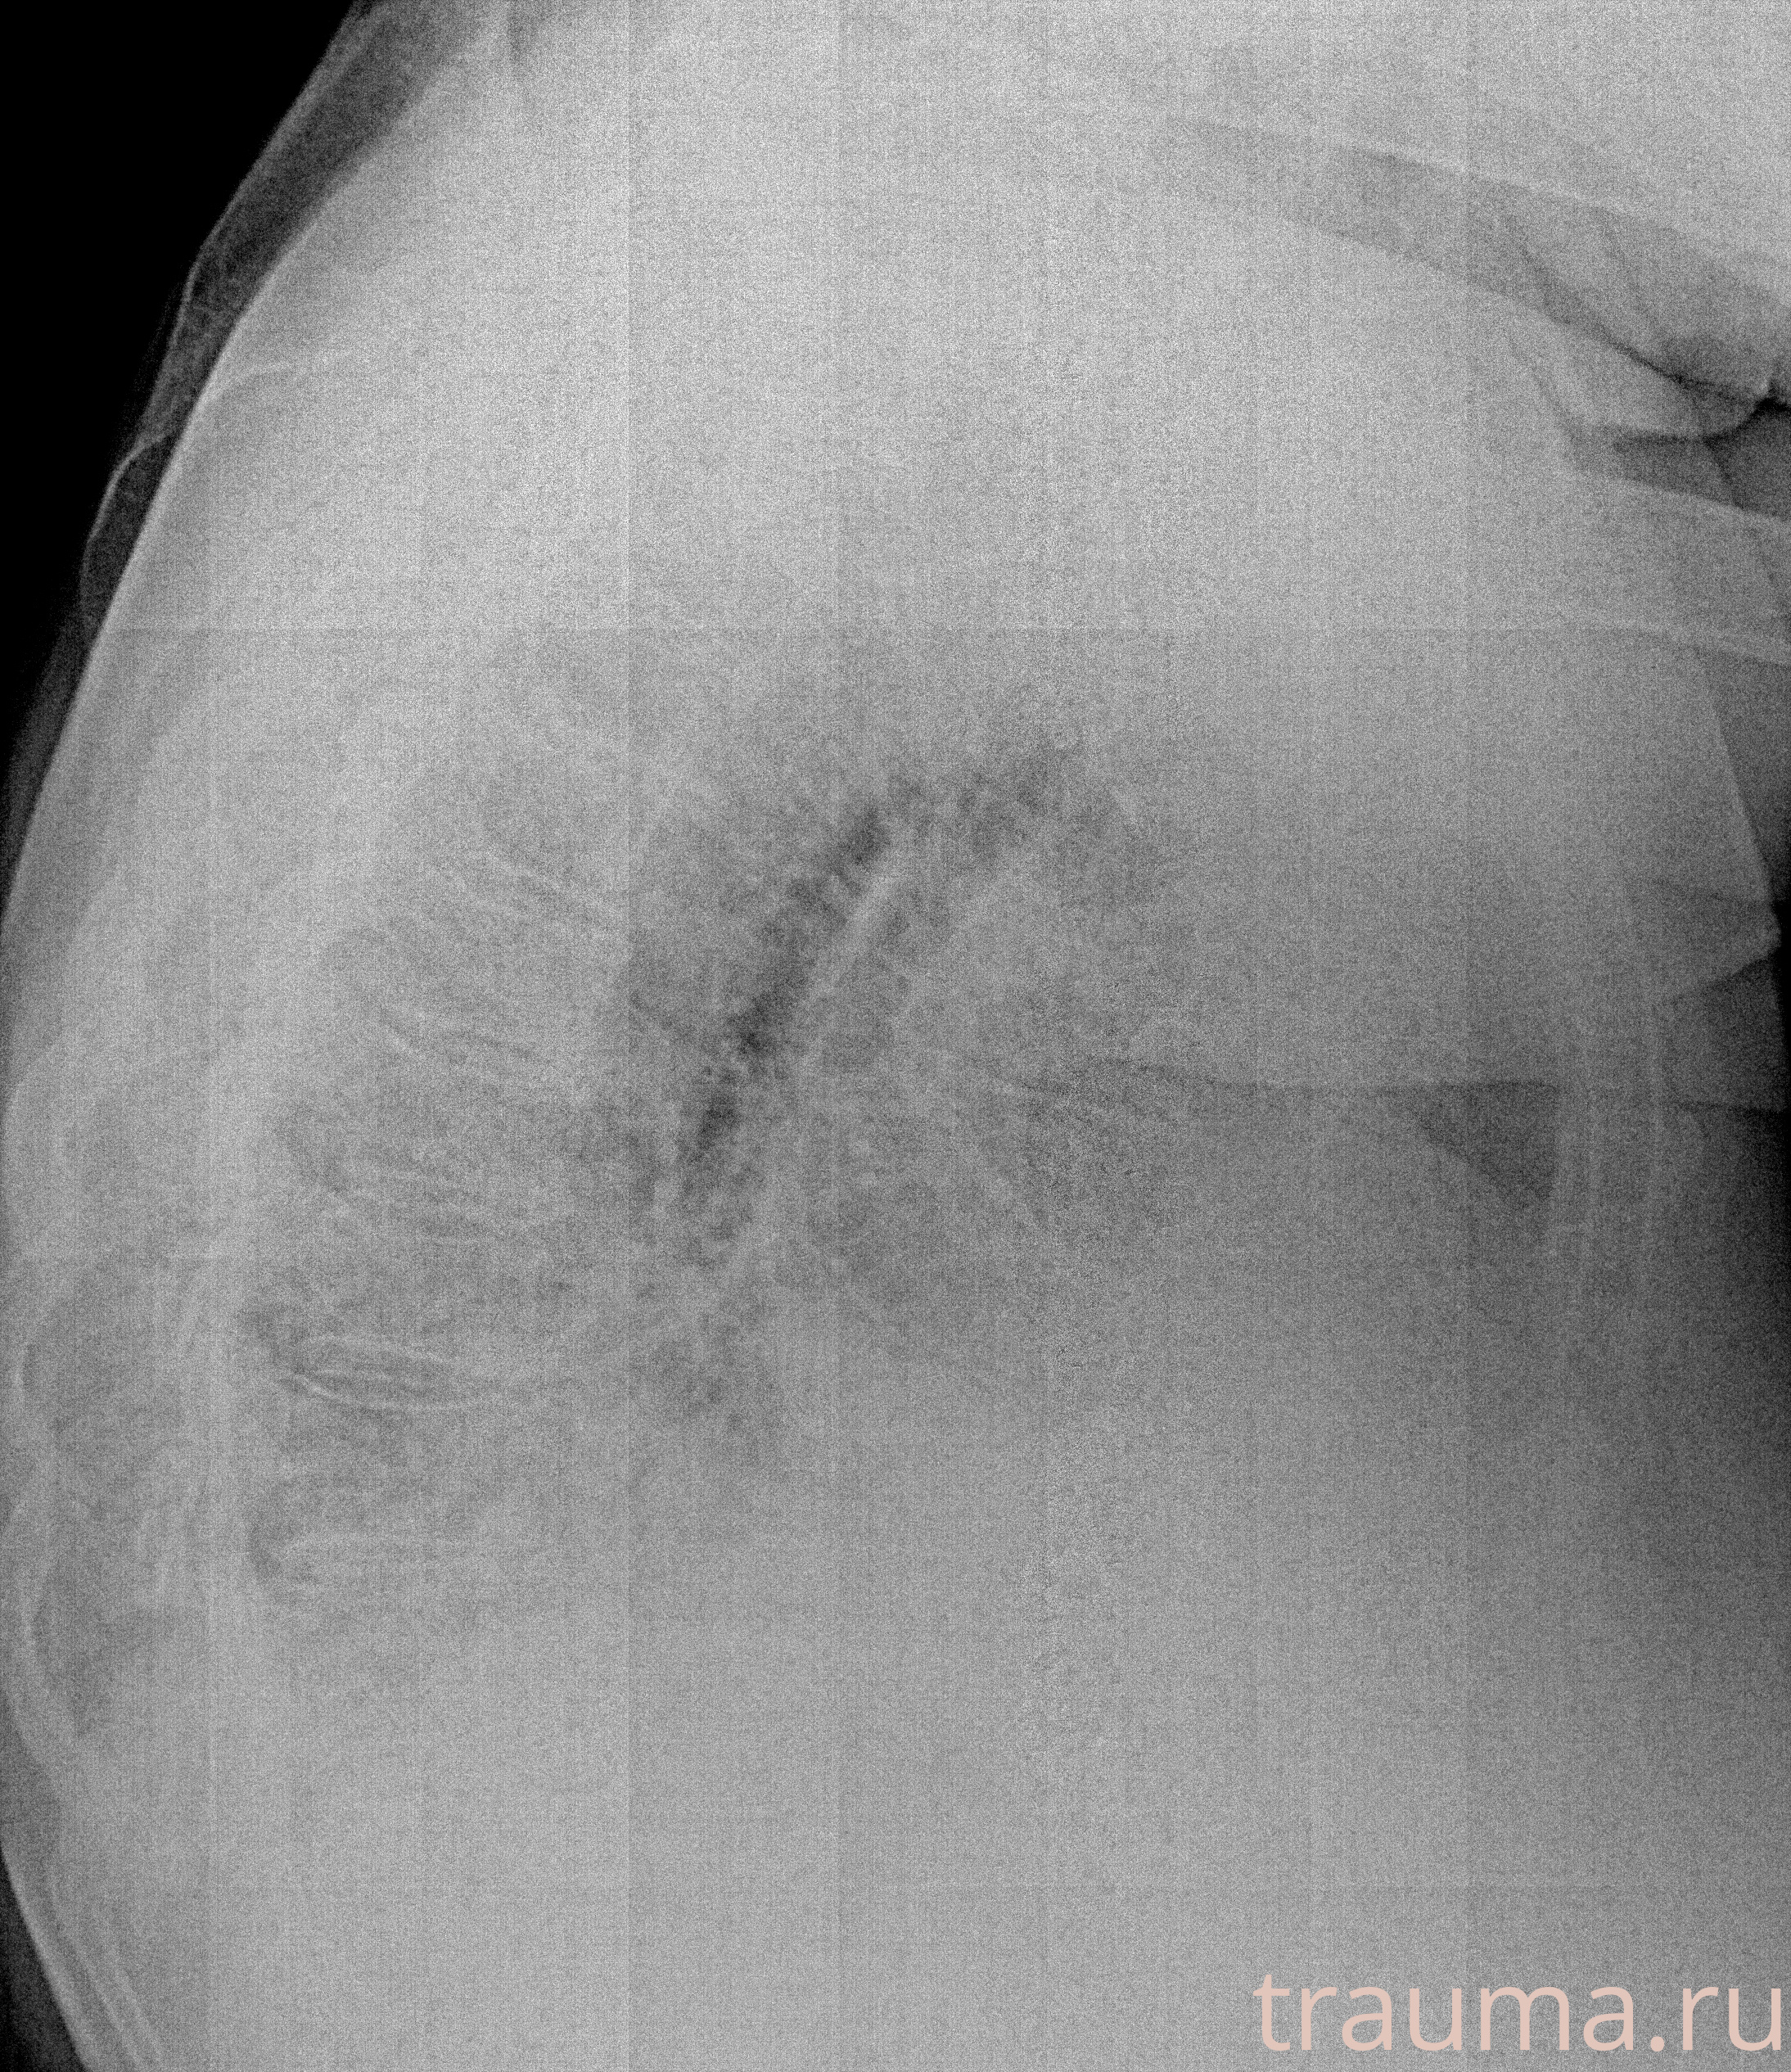

Рентгенограммы

Рентген на дому: по вашему адресу приезжает врач-рентгенолог, травматолог-ортопед с мобильным рентгеновским аппаратом, проводит диагностику травмы или заболевания, делает необходимые рентгенограммы, дает рекомендации по дальнейшему лечению. Получить качественные снимки в домашних условиях возможно благодаря уникальной методике, разработанной МосРентген Центром для института  Склифосовского

при переломе шейки бедра и пневмонии от компании МосРентген Центр - партнера Института имени Склифосовского